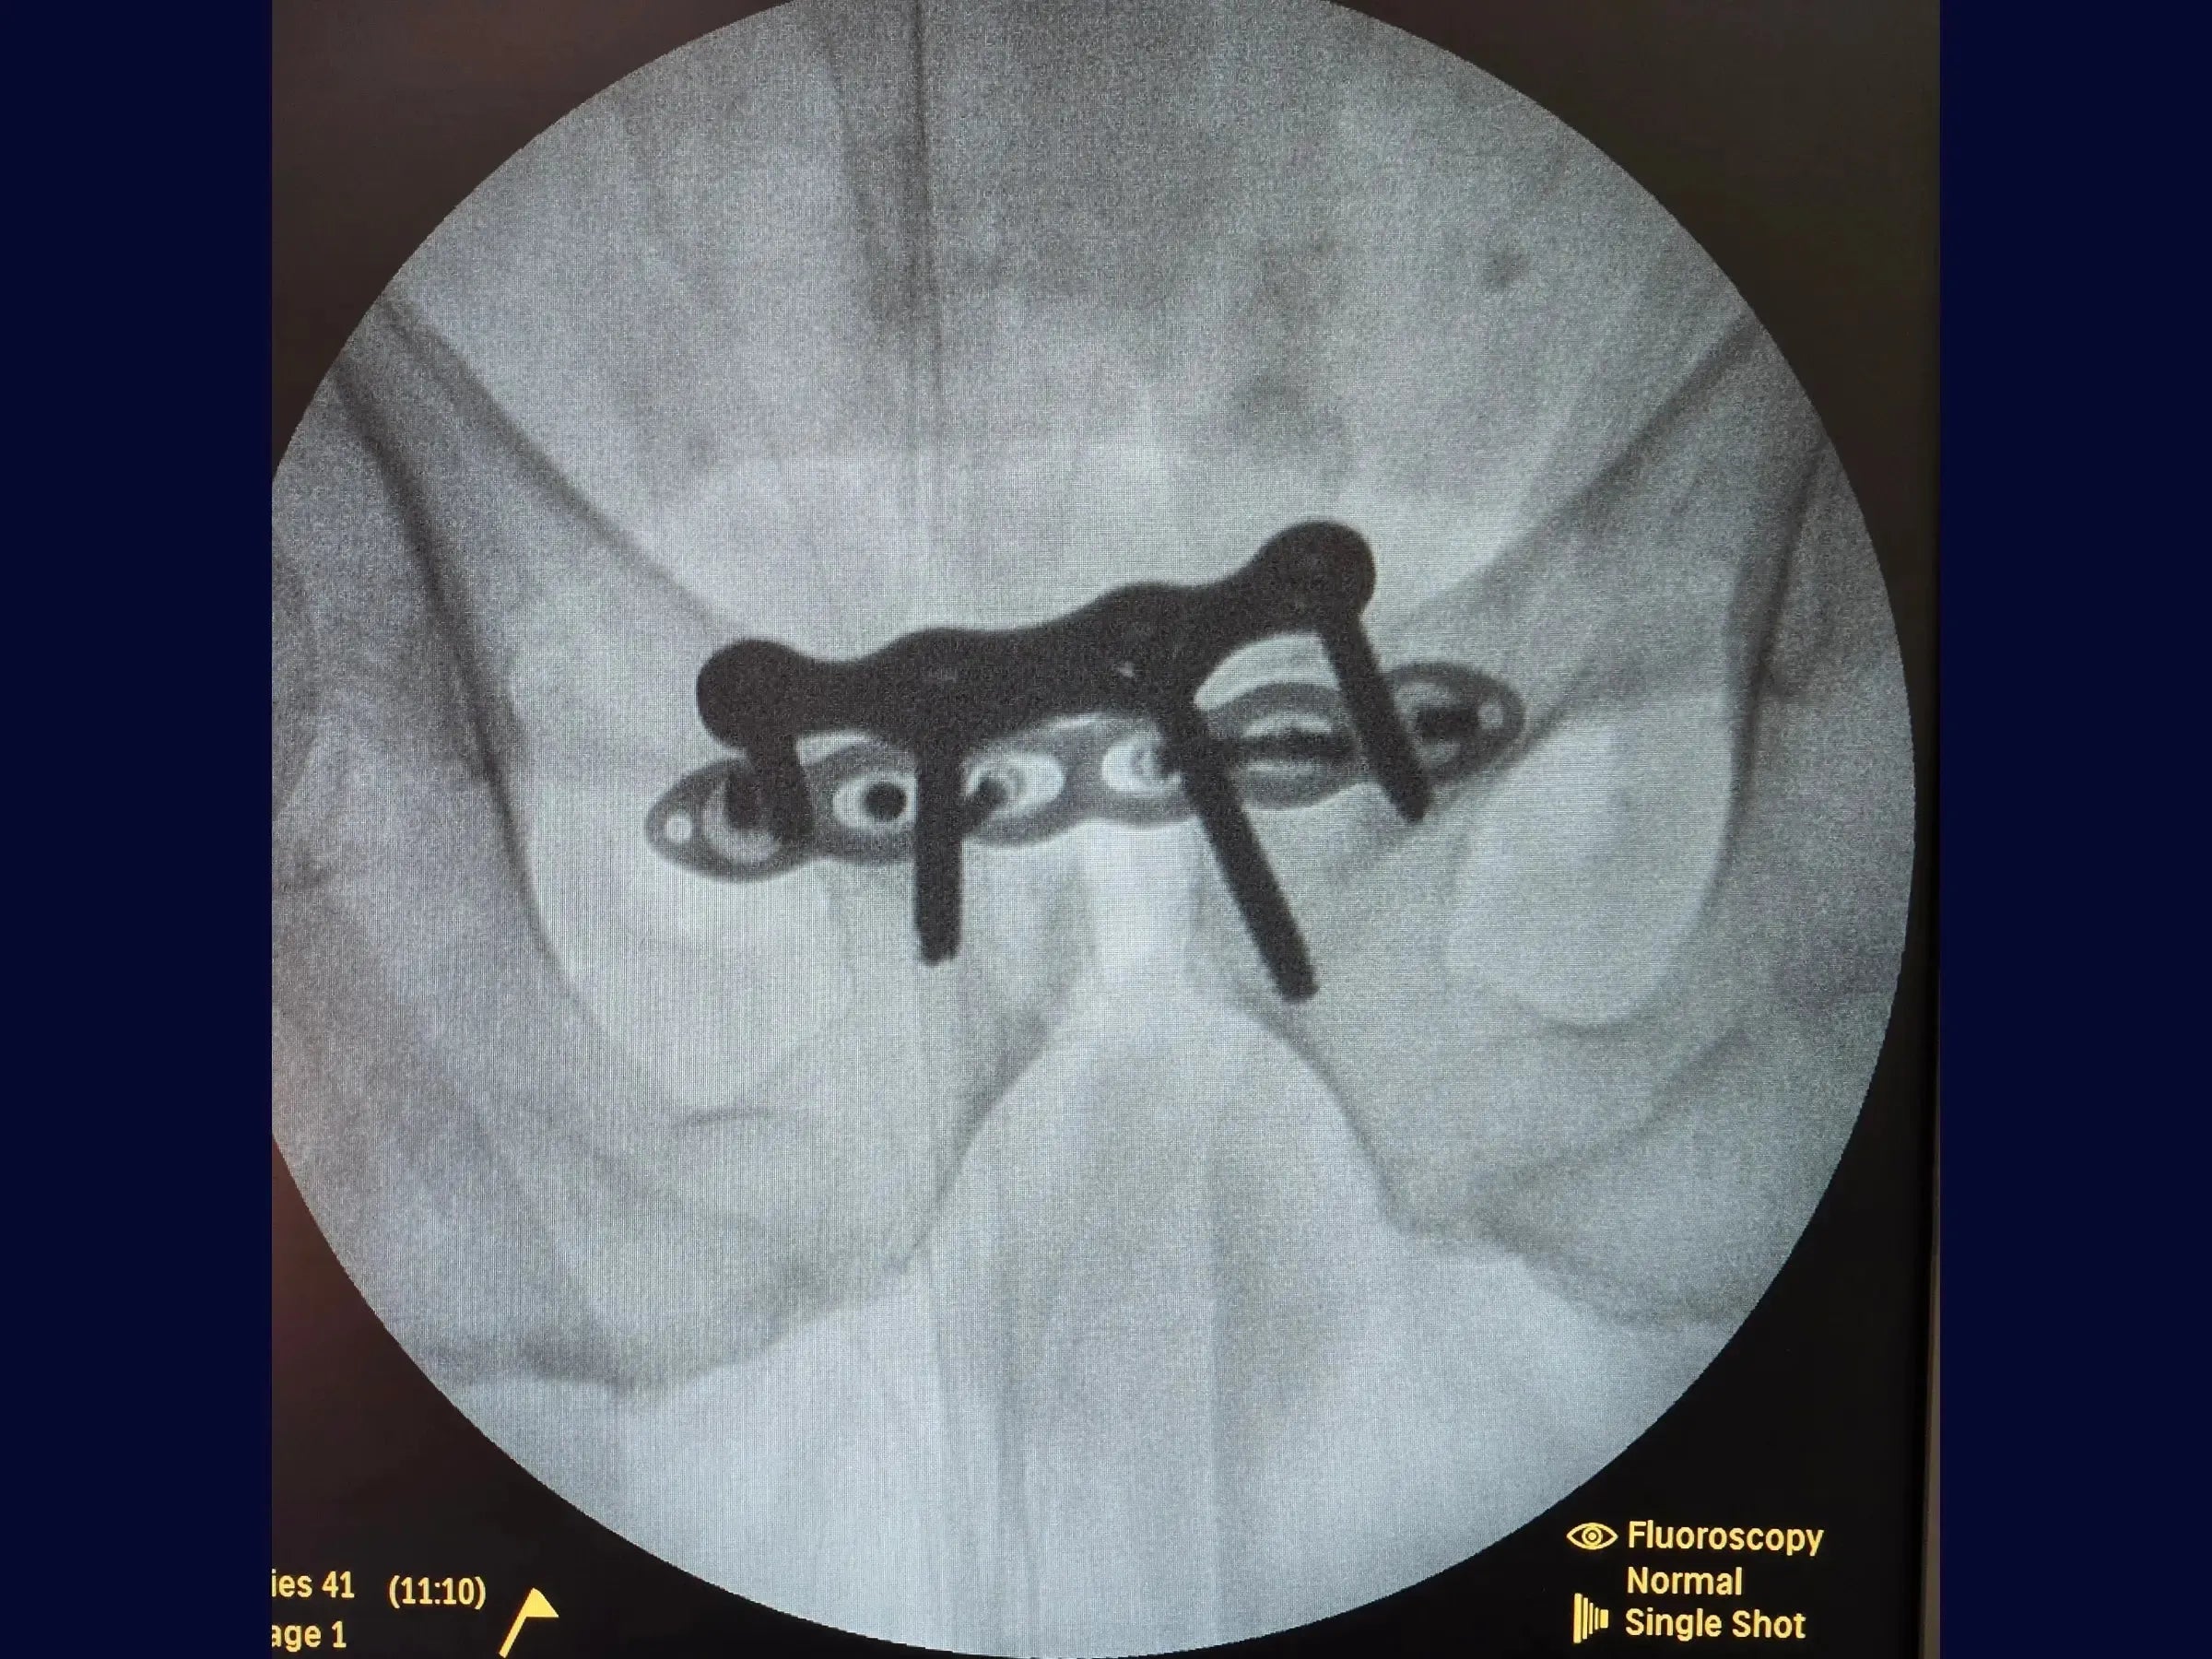

- Redução Provisória: Utilize parafusos temporários, um de cada lado da sínfise, inseridos de anterior para posterior com medição precisa. Empregue uma pinça específica acoplada a esses parafusos para redução e ajuste, controlando o cisalhamento e abertura visualmente.

- Utilização de parafusos temporários para redução controlada.